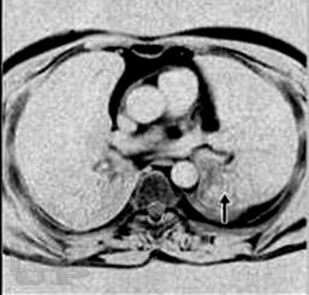

Представлено современное состояние проблемы различных форм злокачественных опухолей бронхолегочной системы, включая и паранеопластические проявления рака легкого. Представлены этиопатогенетические аспекты развития раковой болезни. Даны современные классификации рака легкого. Клиническая картина изложена систематизированно, с алгоритмом дифференциально-диагностического аспекта. Отражены последние достижения и перспективные исследования в диагностике рака легкого. Особое внимание уделено современным методам лечения рака легкого, показаниям и противопоказаниям к применению тех или иных методов лечения, особенно хирургического. Материал сопровождается подробными иллюстрациями.